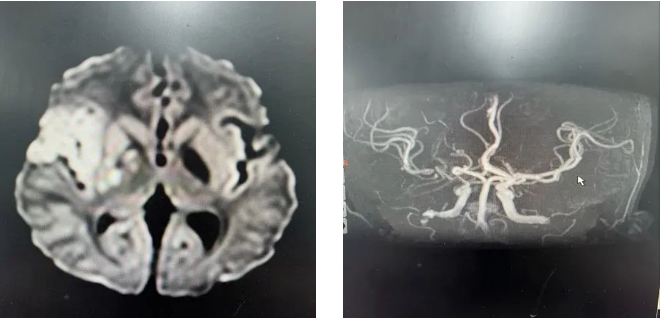

这天中午,12岁的晨晨(化名)跑完200米后突然摔倒,而且左侧肢体偏瘫、抽搐发作、左侧面瘫、意识障碍。随后,120救护车将晨晨送到首都儿科研究所急诊科,头颅CT显示,晨晨的大脑灰白质分界不清,头颅MRI显示为急性脑梗塞,右侧大中动脉闭塞,NIHSS评分9分。

头颅MRI显示急性脑梗塞,右侧大中动脉闭塞

时间就是生命,脑部缺血短时间内如果不能解除,将造成不可逆的神经损害,影响孩子终生。神经内科二病区紧急启动救治方案,主任张建昭立即联系了介入血管瘤科主任申刚,申刚主任当即决定即刻为晨晨进行介入取栓手术。迅速完善脑血管造影后,发现右侧颈内动脉闭塞,决定进行支架取栓,成功取栓后再次造影,提示血管狭窄明显,又植入支架,植入后大脑中动脉通畅。

支架植入后大脑中动脉通畅